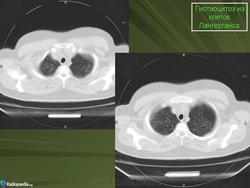

Изменения в позвоночнике наблюдались только в 2-х случаях. Тела позвонков при этом были сплющены до узкой пластинки, имели уплотненную структуру (Рис. 3).

Полисистемный вариант ГКЛ установлен 7 детям в возрасте от 9 мес. до 2-х лет. Болезнь дебютировала астеническим синдромом (вялостью, слабостью, беспокойством, снижением аппетита), длительной фебрильной лихорадкой у 4-х детей, увеличением лимфатических узлов в виде конгломератов у 2-х. Поражение кожи наблюдалось у 3-х пациентов в виде геморрагической петехиальной сыпи, себорейного дерматита волосистой части головы и изъявления естественных складок. Гепатоспленомегалия отмечалась у 3-х (значительно увеличивались размеры селезенки - нижний край определялся в малом тазу), у одного ребенка развился синдром несахарного диабета. В анализах периферической крови в 4-х случаях выявлялся выраженный нейтрофильный лейкоцитоз до 30 тыс/мкл со сдвигом влево, тяжелая анемия, требовавшая заместительной терапии, тромбоцитопения, ускорение СОЭ до 30мм/час. В тяжелом состоянии госпитализировано 6 больных. Диагноз мультисистемный ГКЛ установлен на основании гистологического исследования пораженной ткани (кожи, лимфоузла, кости, селезенки), КТ, МРТ, миелограммы. Хирургическое лечение, спленэктомия, поведено 1 ребенку, в катамнезе без осложнений и рецидива заболевания. Химиотерапию получили 5 детей: протокол DAL-HX-83 (2), протокол LCHII(3). В РДКБ (г.Москва) направлен 1 ребенок с полисистемным ГКЛ: поражение кожи, лимфоузлов, печени, селезенки, легких, костного мозга, множественные костные деструкции; положительный эффект достигнут после блоков химиотерапии с применением кладрибина, цитозара, солу-медрола; в настоящее время на поддерживающей терапии. В катамнезе у 6 детей с полисистемным ГКЛ отмечены осложнения: несахарный диабет (3), компрессионный перелом позвоночника (2) (рис. 4), неполная клиническая ремиссия (2).

Рис. 4.Больной Б.С., 14 лет. МРТ позвоночного столба. Компрессионный перелом тел Th2, Th5, Th6, Th8, Th12 позвонков Iстепени на фоне ГКЛ.